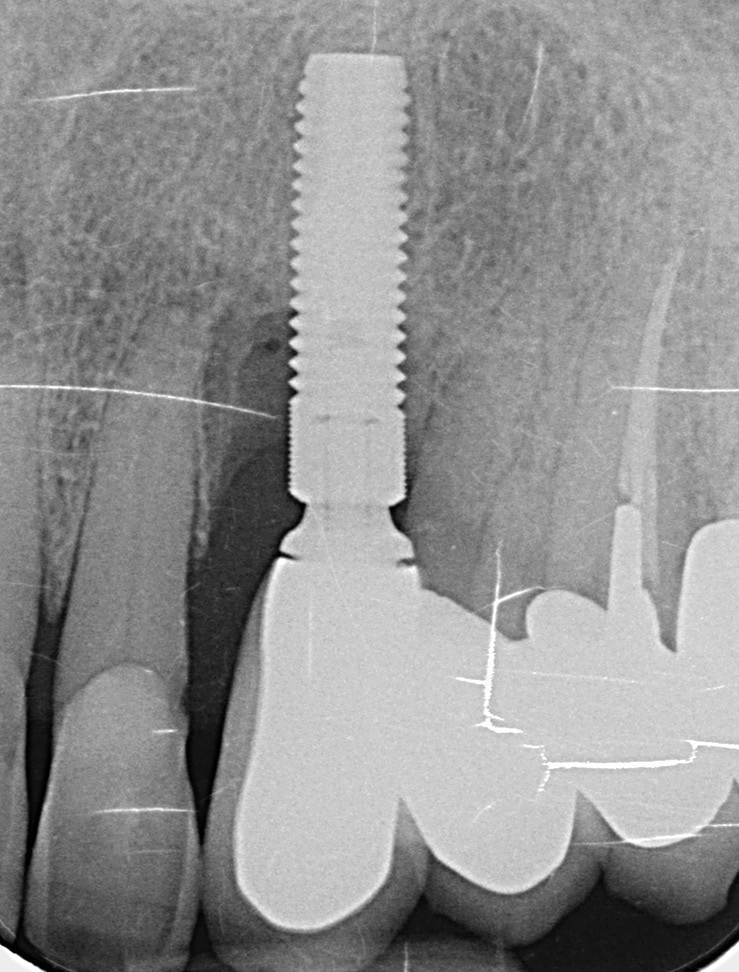

L’implant

- Site 23

- Mis en place il y a 12 ans